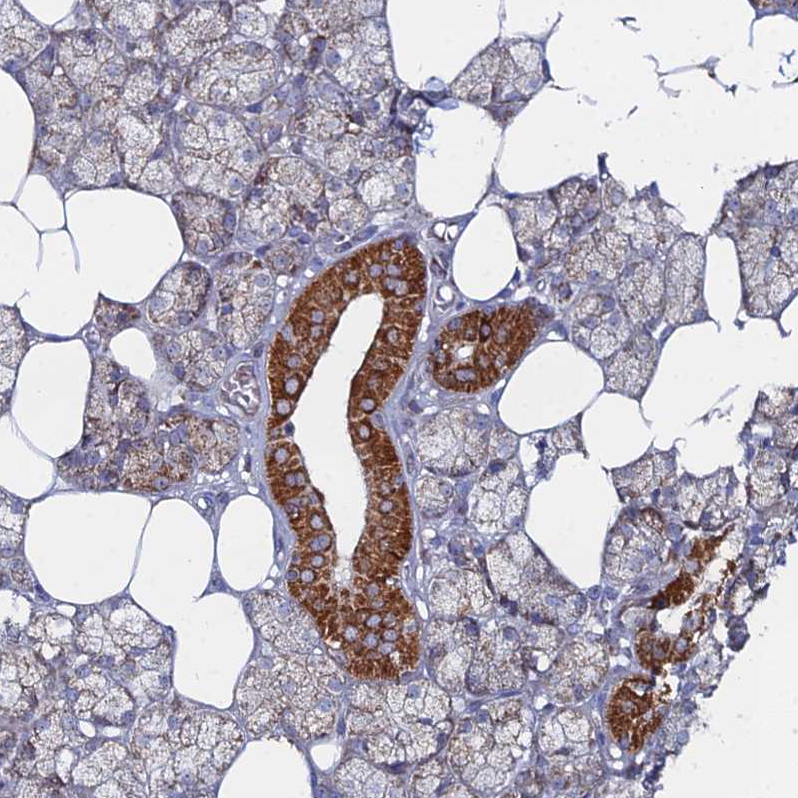

Immunohistochemistry analysis in human heart muscle and pancreas tissues using HPA045119 antibody. Corresponding MPC1 RNA-seq data are presented for the same tissues.